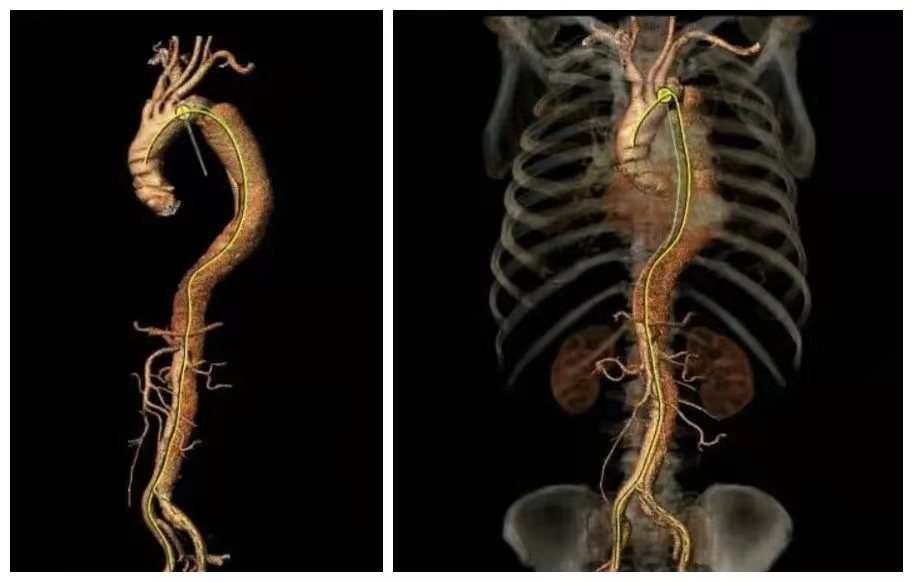

患者男性,67歲,因咳嗽、胸部不適就醫(yī),CT檢查提示主動(dòng)脈夾層(B型)、主動(dòng)脈弓及腹主動(dòng)脈硬化,局部形成鈣化斑塊,隨以“主動(dòng)脈夾層瘤”急診收住。

時(shí)間就是生命,我院立即開辟綠色通道,以最快捷、最高效的就診流程,積極完善術(shù)前準(zhǔn)備,在局部麻醉下經(jīng)腹股溝股動(dòng)脈穿刺行“主動(dòng)脈夾層腔內(nèi)修復(fù)術(shù)”。西安交大一附院血管外科專家、主任醫(yī)師馮駿教授親臨指導(dǎo),手術(shù)順利,破口封閉,血管真腔開通,整個(gè)手術(shù)過程歷時(shí)約30分鐘,患者生命體征穩(wěn)定,術(shù)中、術(shù)后未訴不適;術(shù)后第二天,患者可下床活動(dòng);術(shù)后第三天,患者康復(fù)出院。